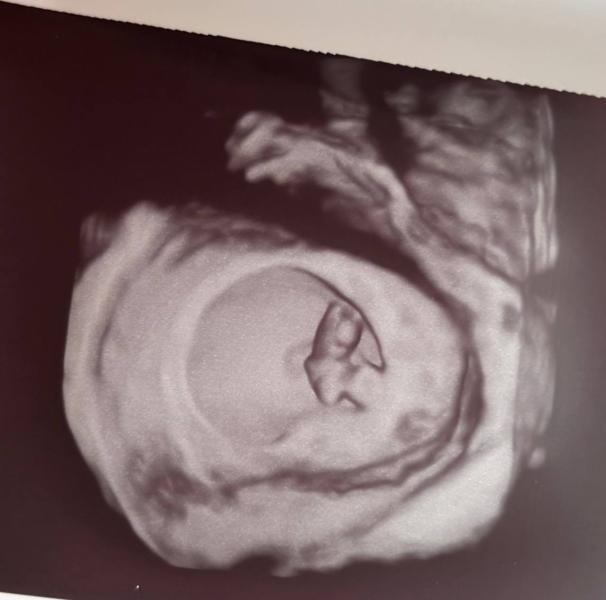

8 недель и 3 дня😍

Снимок в 3Д уже видно личико и ростут ножки и ручки, уже похож на человечка🥰

Ктр 1,6 см

Жм 5,4 мм

Пя 4,4 см

Сердц + 158 уд/мин

Какая бусинка маленькая 🥰первый раз вижу в 3д на таком сроке маленьком